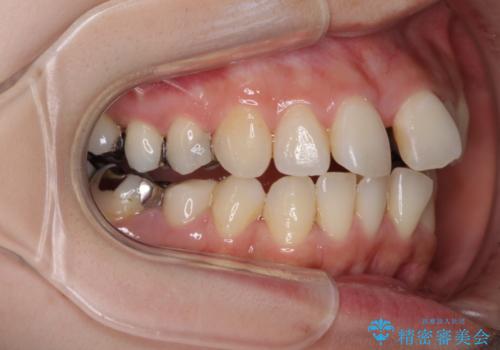

- 上下のデコボコと奥歯の咬みにくさを気にして来院された患者様です。

上顎骨の幅が下顎骨よりも小さいので、拡大装置により骨幅を広げて上下関係を改善し、その後インビザラインにて歯並びを整えることとしました。

上下の骨幅を改善したことで、スムーズに歯列矯正を行うことができました。

矯正治療中に近医で銀歯を外す治療を開始したため、治療後に奥歯の咬み合わせが不十分ですが(こちらは近医での治療により改善するとのこと)、歯列と咬み合わせが改善され、患者様には大変満足していただきました。